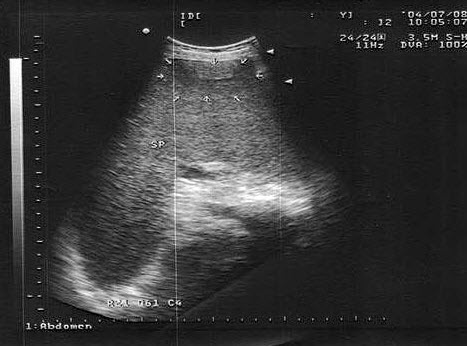

3、单项选择题

男,18岁,外伤1小时就诊。结合超声声像图,诊断为()

A.脾外伤血肿

B.脾淋巴管瘤

C.膈下积液

D.脾皮样囊肿

E.脾血管瘤